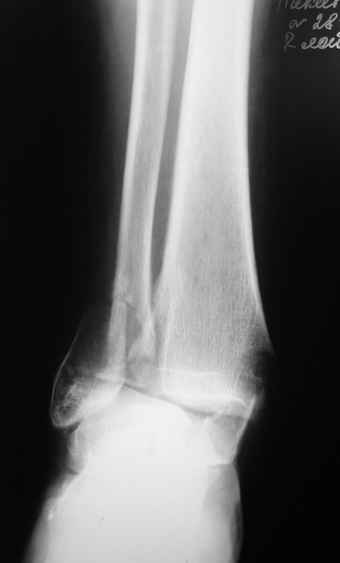

Уважаемые коллеги,Поступила пациентка, 59 лет, с переломом лодыжек. В связи с выраженным отеком при поступлении наложено скелетное вытяжение. Грубая деформация устранена. Планировался остеосинтез пластиной, винтами. Однако больная сообщила, что страдает болезнью Виллебранда, и что гематолог рекомендовал, по возможности, избегать оперативных вмешательств из-за высокого риска кровотечений. По этой причине планируем закрытый остеосинтез с применением аппарата Илизарова. Какие опасности и осложнения могут встретиться в связи с данным сопутствующим заболеванием?

Спасибо за обсуждение нашей пациентки. Применили аппарат Илизарова, место перелома не открывали.. Прошло около двух недель. Кровотечения не было ни во время операции, ни после. Снимки представлю позже, пациентка выписалась и увезла их с собой.